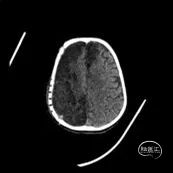

2023年11月,因交通事故导致“特重型颅脑损伤”,在当地医院行“硬膜外血肿清除术及去颅骨骨瓣减压术”,术后予以降颅压等对症支持治疗,术后持续昏迷。

2024年1月复查头颅CT示交通性脑积水,于广东省第二人民医院行侧脑室腹腔分流术,术后病情稳定,继续于外院进行神经康复治疗,遗留意识朦胧、四肢肌张力增高、生活不能自理。

患者为进一步明确诊治,以“颅骨缺损、脑外伤后恢复期、脑积水术后”于2024年5月15日收入广东省第二人民医院神经外科。

专科查体

右侧额颞顶部颅骨缺损,范围约14*16cm,减压窗塌陷;神志呈睁眼昏迷状;气管切开状态;双侧瞳孔等大,直径2.0mm,对光反射灵敏,眼球可自主游动;四肢肌张力增高,肌力2级;生理反射存在,病理反射未引出。